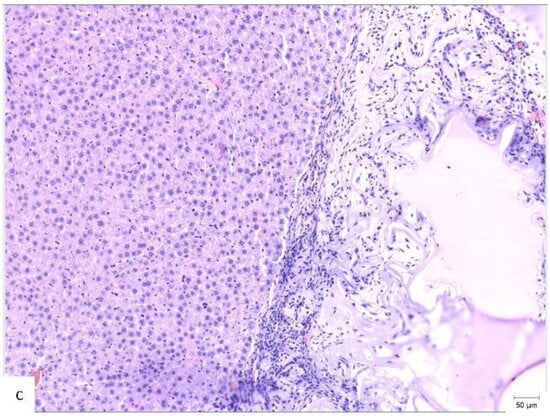

A comparison of the histopathological findings in the hepatic tissues of the three experimental groups on PO day 50 can be seen in Figure 4.

Figure 4.

Histopathological appearance of hepatic tissue from the three experimental groups at PO day 50; Hematoxylin and Eosin staining, ×10 magnification, the scale bar (right lower corner of each picture) is 50 µm. (a) Study group (CA + PLA patch): Section shows dense inflammatory infiltrate composed of both lymphocytes and scattered polymorphonucleated neutrophils concentrated around the adhesive interface and extending into the adjacent hepatic parenchyma. This mixed inflammatory reaction is indicative of an acute-on-chronic tissue response to the foreign material. Fibrosis was also detected, characterized by fibroblast proliferation and collagen deposition, consistent with early reparative remodeling. (b) Control group (electrocautery): Normal hepatic architecture is preserved, with no evidence of inflammatory infiltrate, necrosis, or fibrosis. The absence of immune cell recruitment indicates minimal tissue damage or foreign body reactions associated with electrocautery hemostasis. (c) Comparison group (TachoSil®): Mild, patchy lymphocytic infiltration was observed at the interface between the hepatic parenchyma and the remaining hemostatic material. The right portion of the image shows residual TachoSil matrix appearing as pale eosinophilic, acellular fragments, consistent with a fibrin-rich thrombin/fibrinogen composite undergoing resorption. No neutrophilic infiltration or fibrosis was evident.